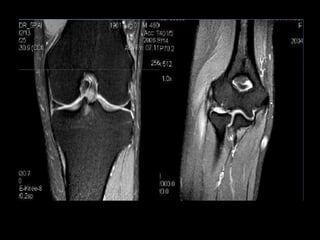

• TI muito baixo, fazendo com

que a gordura não dê sinal.

• Excelente para estudo

musculoesquelético, pois

evidência muito bem as

lesões com edemas e

inflamações.

STIR

• TI muitobaixo, fazendo com que a gordura não dê sinal. • Excelente para estudo musculoesquelético, pois evidência muito bem as lesões com edemas e inflamações. STIR